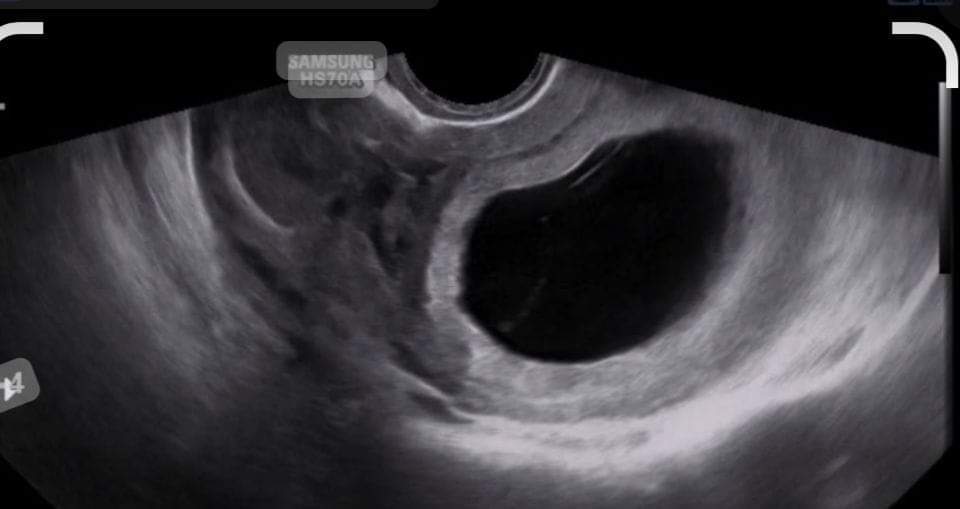

œuf clair traitement naturel. grossesse œuf clair, blanc, traitement naturel